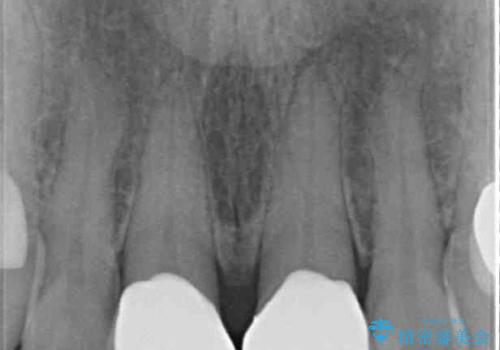

色彩や形態が大きく改善されたことはもちろん、虫歯によってしみていた症状もなくなり、患者様には大変満足していただきました。